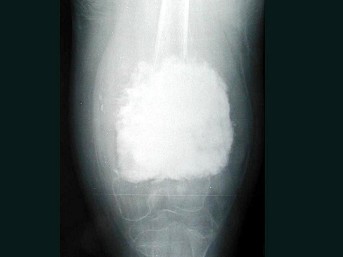

女,10岁,左大腿疼痛,夜间加重,肿胀明显,结合图像,最可能的诊断是()

• C.骨肉瘤